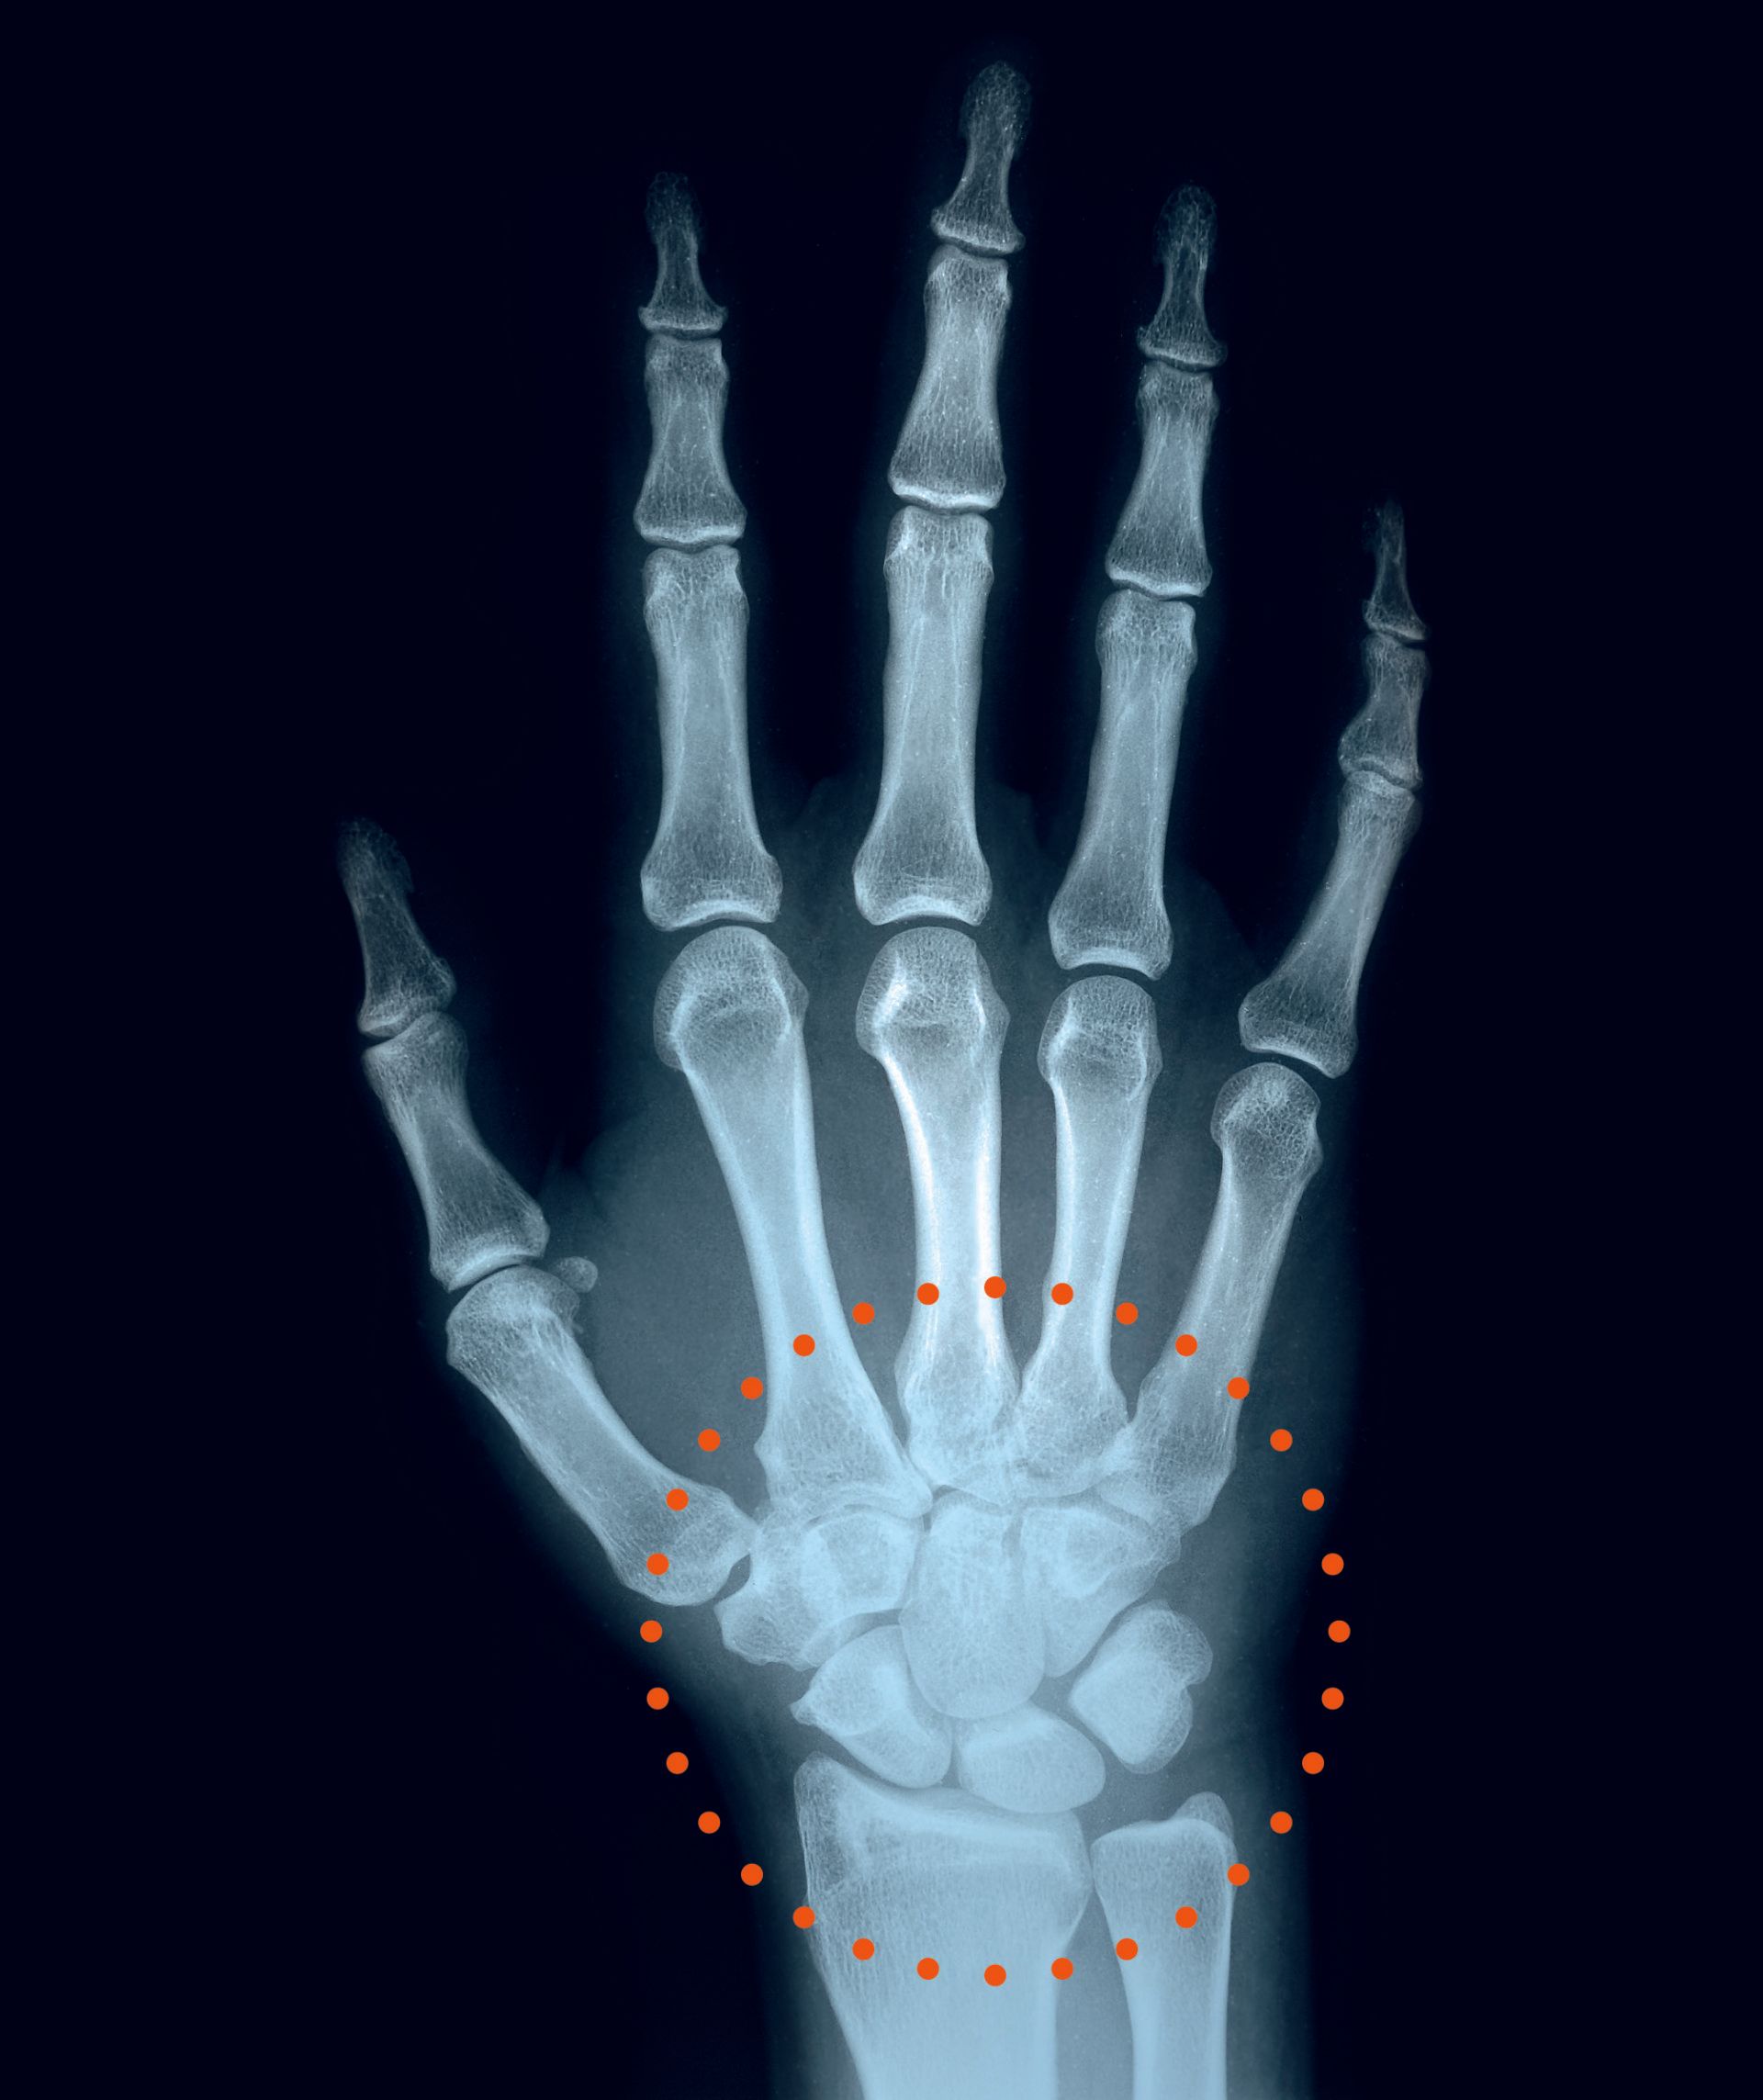

Notfallorthese zur Stabilisierung und Immobilisierung des Handgelenks

Das entwickelte orthopädische Hilfsmittel ist als eine Notfallorthese konzipiert und aufgrund der einfachen und kostengünstigen Herstellung zum primären Einsatz für eine großflächige Patientenversorgung bestimmt.

Vom Konstruktionsprinzip her stellt Orthostruct in ihrem Ausgangszustand eine ebene, einheitliche und achtförmige Schiene dar, die aus zwei symmetrischen Polsterungsflächen sowie einem metallischen Stabilisierungskern besteht und über drei Befestigungsgurte fixierbar ist. Die Verformung der Orthese in eine behandlungsadäquate Zweckform erfolgt durch eine manuelle Anpassung und erfordert keinen zusätzlichen Werkzeugeinsatz. Die gewählte Verbundwerkstoffkombination ist widerstandsfähig, leicht, atmungsaktiv, wasserresistent und zudem durchlässig für Röntgenstrahlung. Aufgrund ihrer vorteilhaften Ausführungsform kann die Orthese für die Behandlung sowohl der rechten als auch der linken Hand eingesetzt werden.